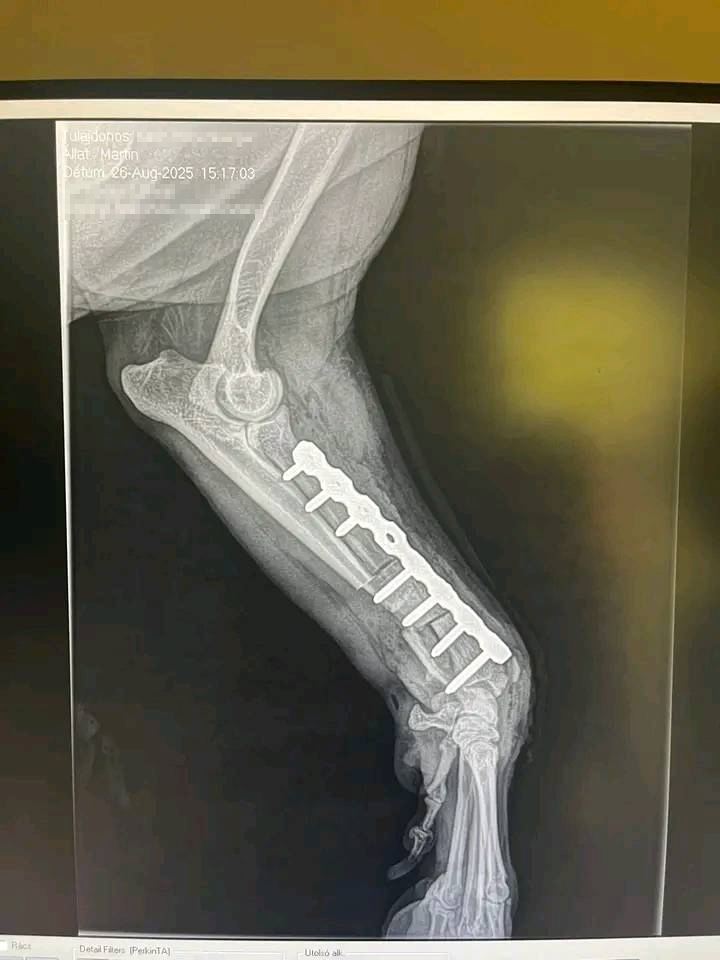

Die Bilder (von mir anonymisiert)

- Der Hund auf den Bildern heißt Martin, ist ein Rottweiler und wird von Karin Hohenberger versorgt.